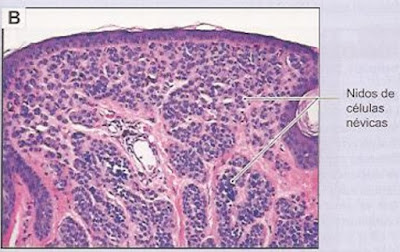

11. Nevo melanocítico